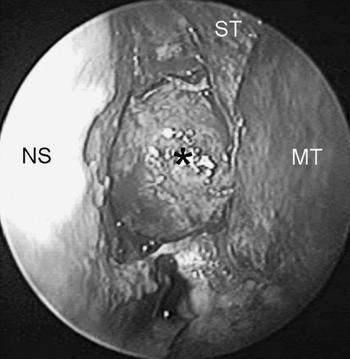

Tommy Hilfiger Crossbody Canvas Logo Women's Black+White Bag, Organised haematoma of the sphenoid sinus mimicking a,

Organised haematoma of the sphenoid sinus mimicking a, ケンゾー KENZO バッグ メンズ ブラック Business Bags